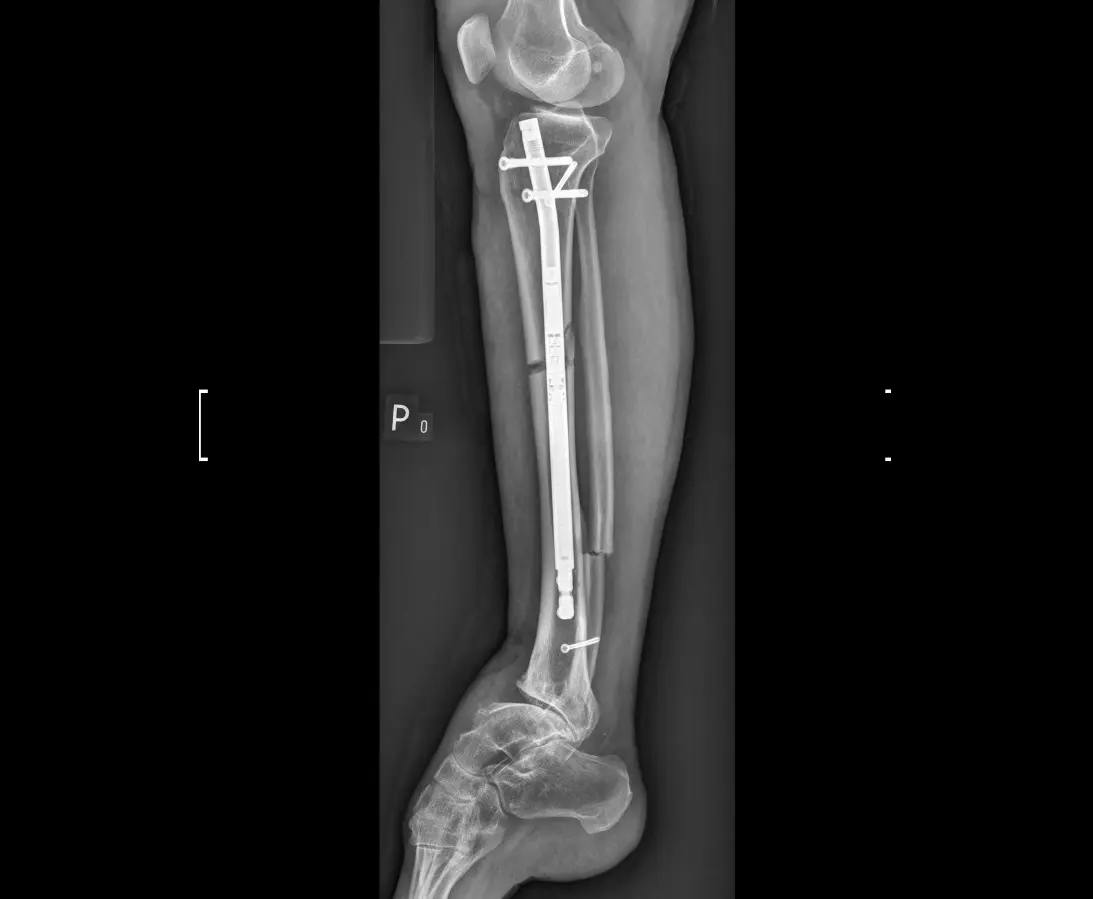

X-ray of the tibia of a patient after limb lengthening surgery.